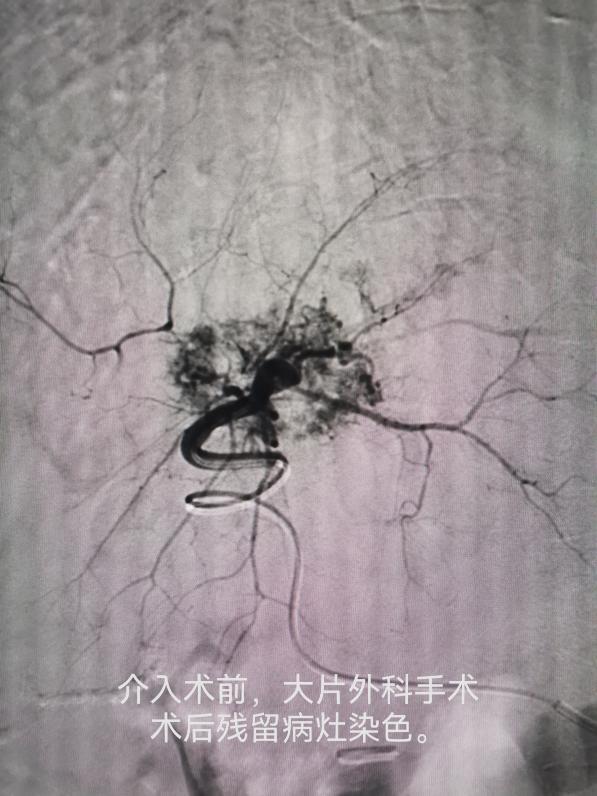

车能雨教授病例展示:

病例一:刘先生,男,55岁,患肺癌,经过三次介入微创手术+三次细胞治疗+靶向治疗,肺癌缩小90%,全身脊柱转移灶得到控制硬化,全身剧痛消失,处于NED状态。